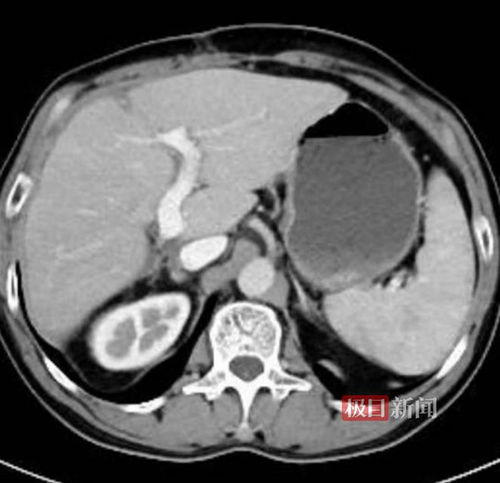

儿童吸入二手烟容易引发支气管炎、哮喘等疾病;女性长期接触则可能增加鼻咽癌、乳腺癌等风险。更令人痛心的是,一名26岁的男性因工作环境被迫吸二手烟4年,最终查出高危肺结节,疑似肺癌。

面对二手烟的危害,我们不能掉以轻心。特别是孕妇、儿童及慢性呼吸道疾病患者等脆弱人群,更应远离二手烟环境。若无法完全避免,可要求吸烟者到室外吸烟,并加强室内通风。定期体检(如低剂量CT)是早期发现肺结节或癌变的有效途径。